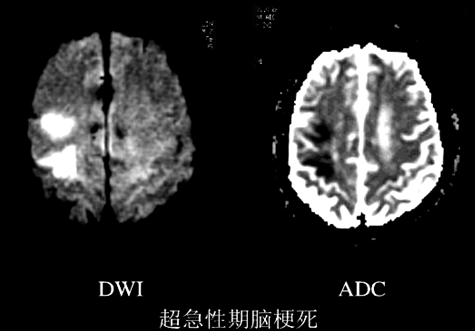

①超早期脑梗死的诊断

①脑脓肿:脓腔于DWI呈均匀高信号,ADC低信号--弥散受限,与脓液的高粘滞度和脓肿的多细胞性有关。